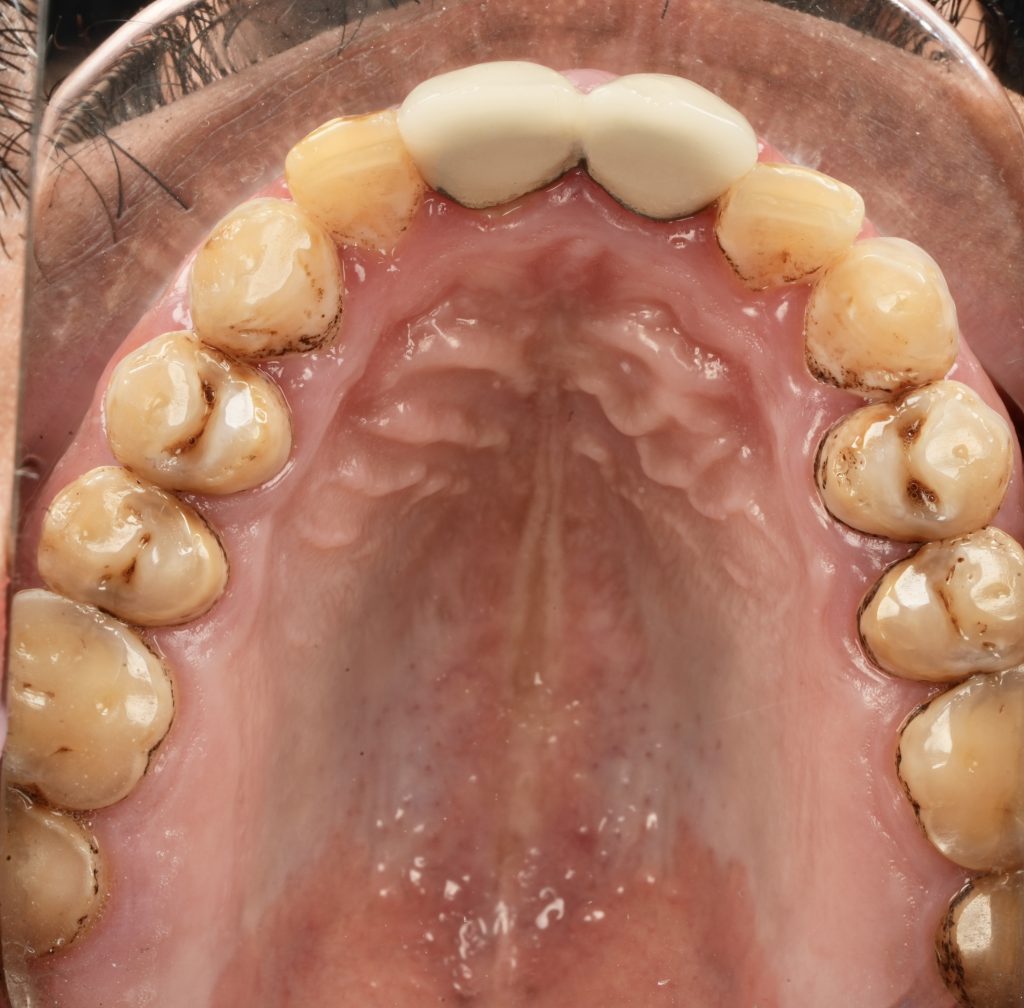

Each veneer was etched with 9 % HF acid for 20 seconds, silanated, and dried. Teeth were treated with 37 % phosphoric acid and universal adhesive (Clearfil Universal Bond Quick). Light-cure resin cement (Variolink Esthetic LC) was applied under full-arch rubber-dam isolation. Excess cement was removed and polymerization performed for 40 s per surface (Fig 4).